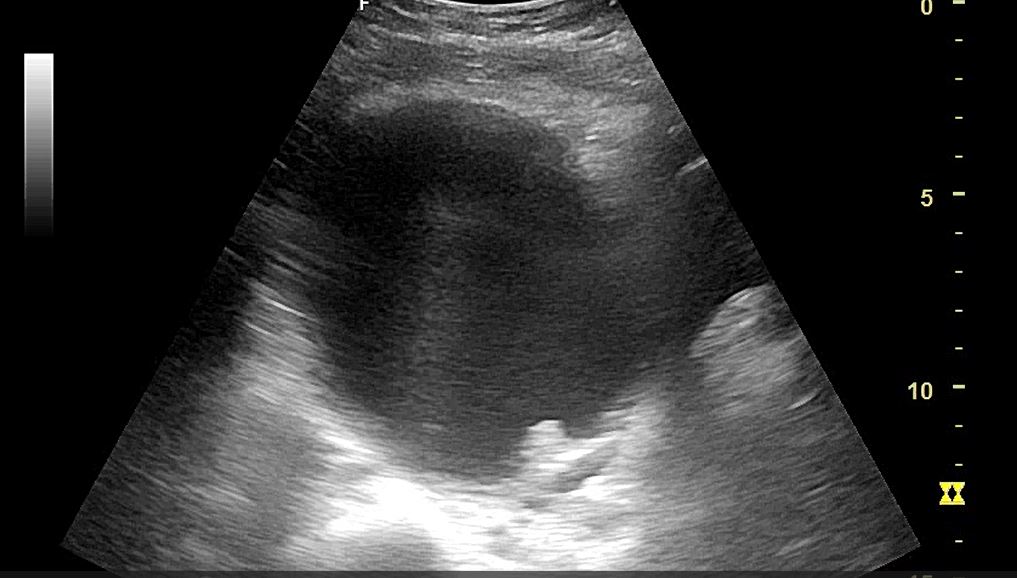

Hallazgos ecográficos

Se objetiva masa vs pólipo intravesical de bordes irregulares, de aspecto heterogéneo de unos 12 x 12 cm.